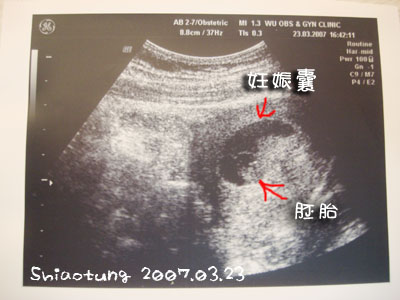

進去以後醫生就馬上要我躺在床上照超音波。

醫生說寶寶沒問題,

但是要我不要太常走動,

因為我腹部中間在痛,

他說那是子宮圓韌帶拉扯造成。

照好超音波下來,

醫生說:要記得自己是孕婦啦!你看我才剛坐下,你也坐下了。

又說:盡量要把動作放慢,前三個月還沒那麼穩定,要多注意一點。

很不會看吼?

醫生沒講我也不知道胚胎在哪?

哈哈哈哈哈...

等他越來越大吧!